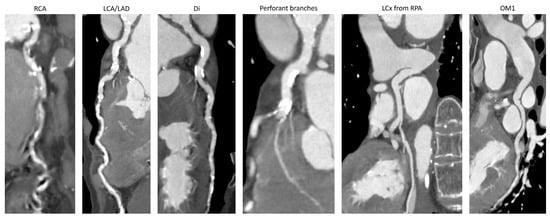

CT Detection of an Anomalous Left Circumflex Coronary Artery from Pulmonary Artery (ALXCAPA) in 81-Year-Old Female Patient

2. Case Description